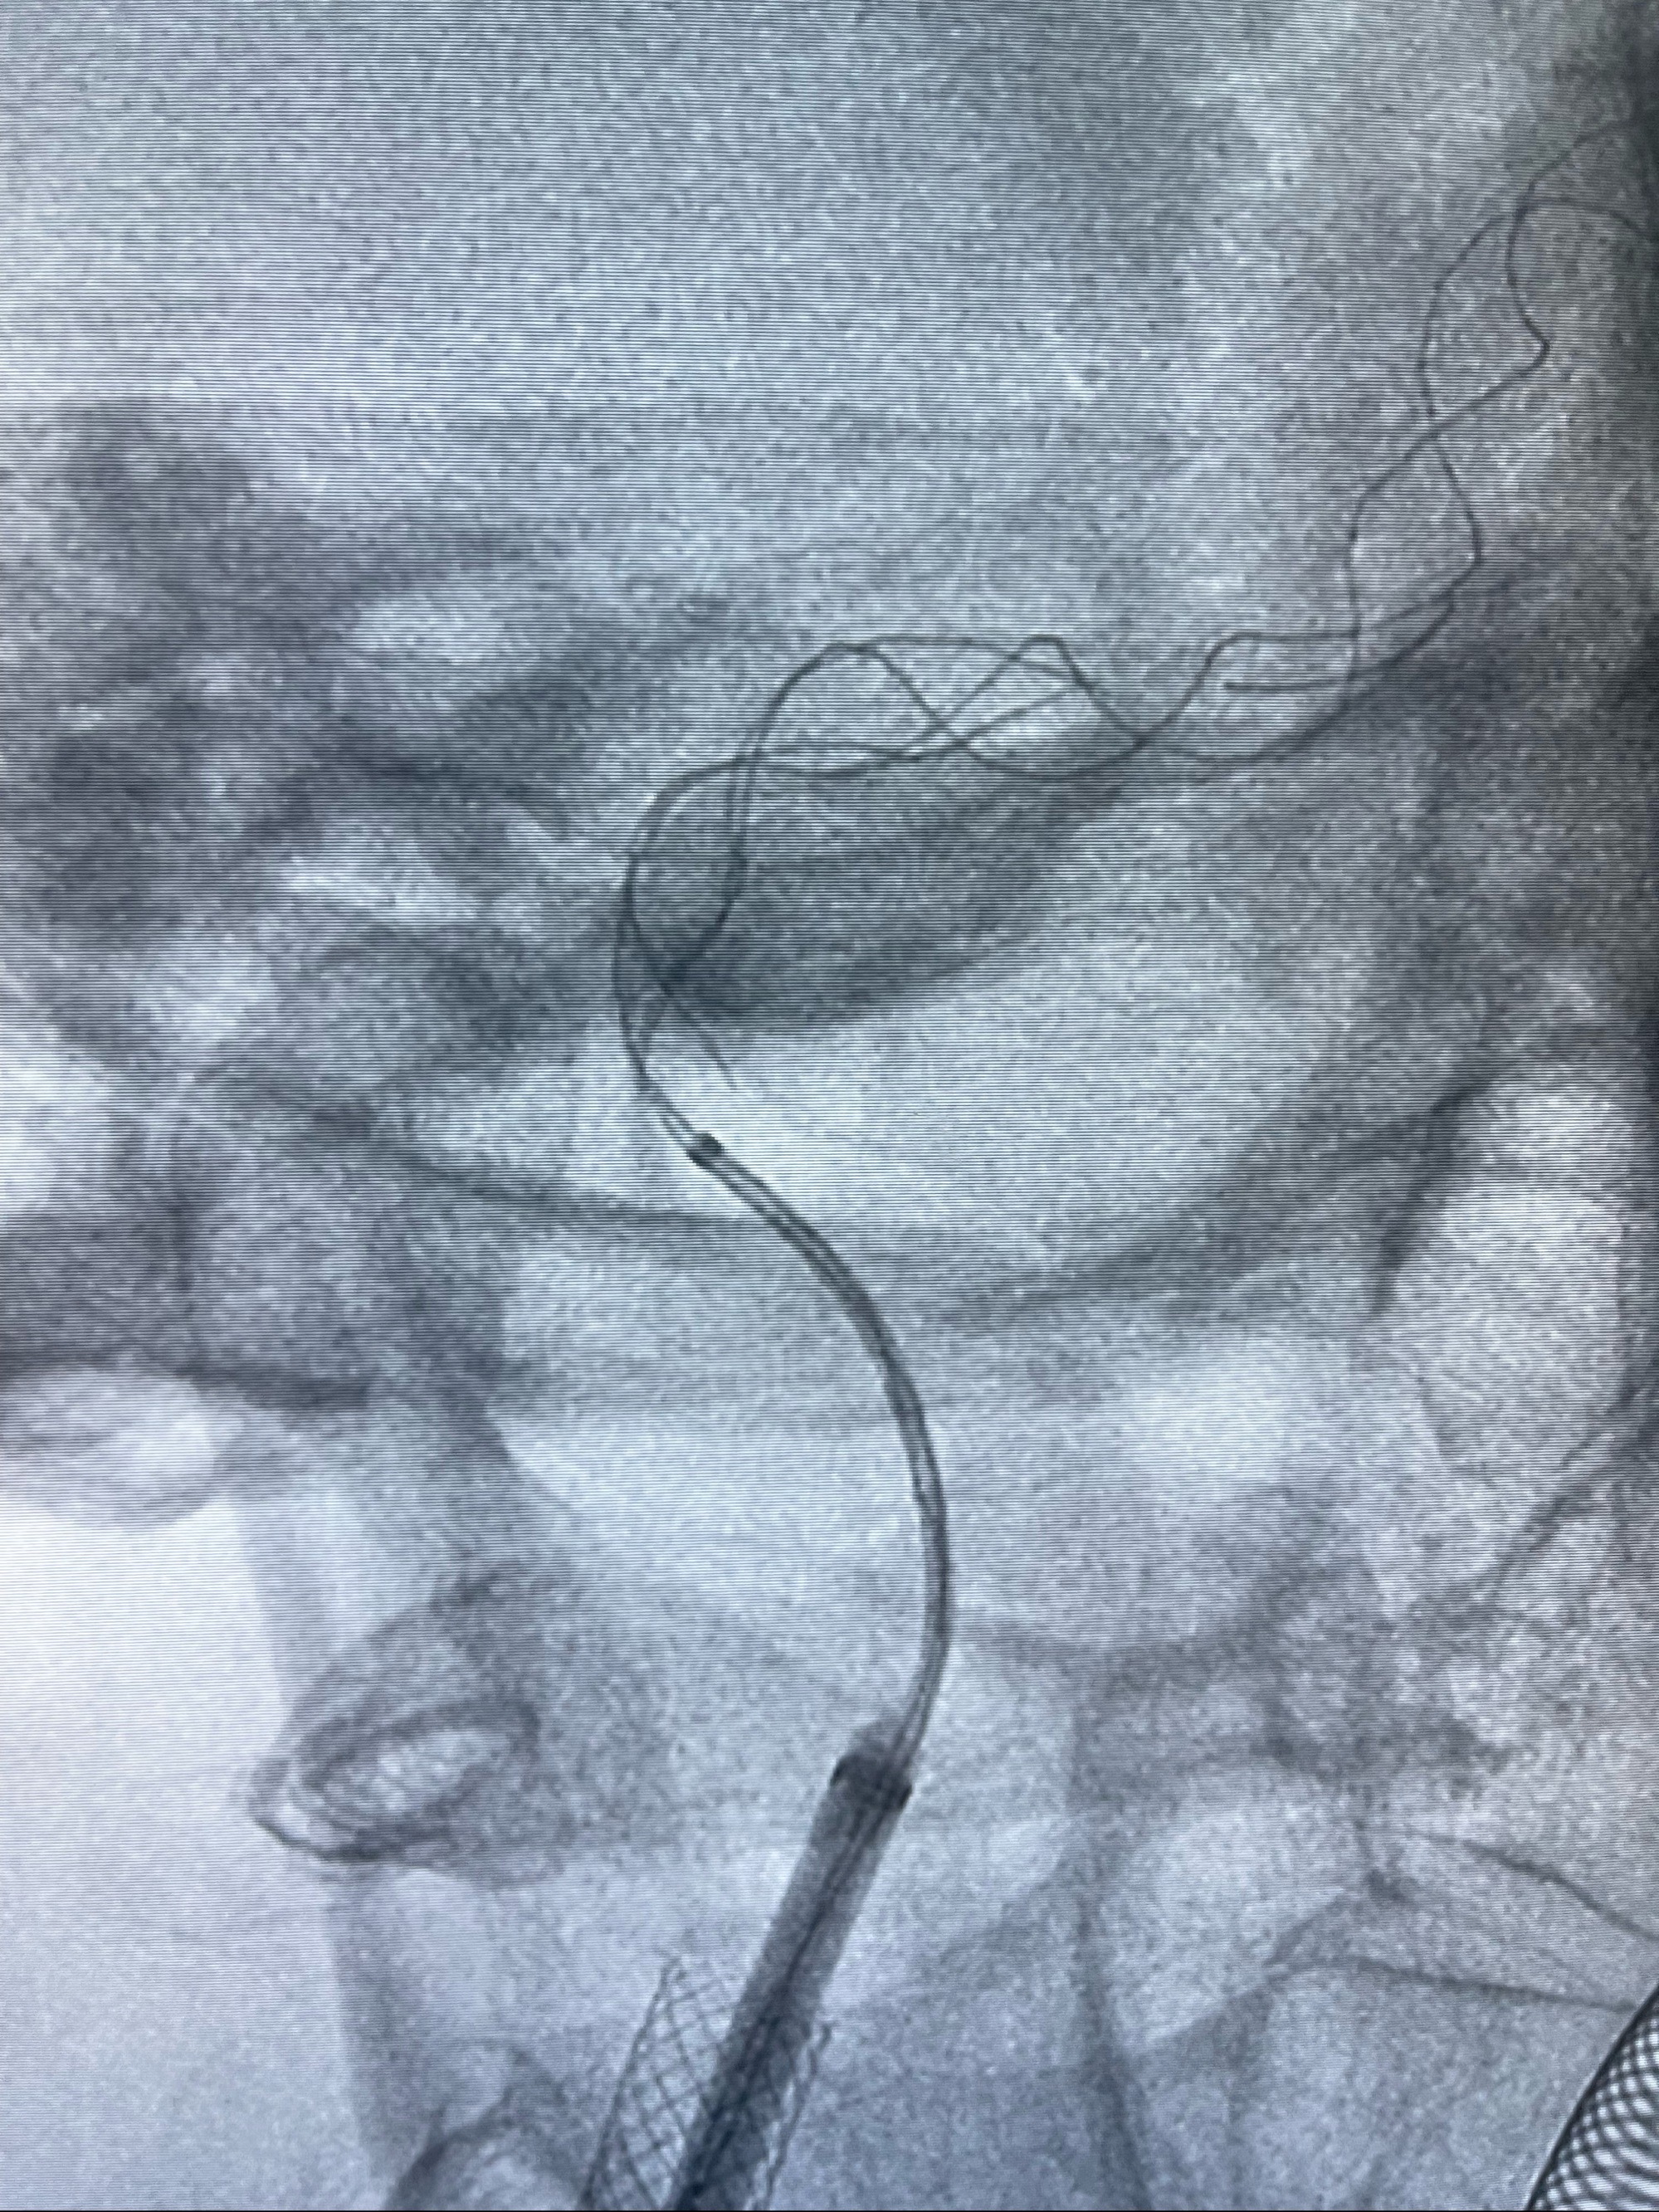

路径图下,5.5-50mmLeo支架导管在微导丝引导下超选择性插入远段Leo支架内

两枚支架部分重叠

多次确认支架位置及打开贴壁情况

支架完全打开,近心端位于原颈动脉支架远心端内